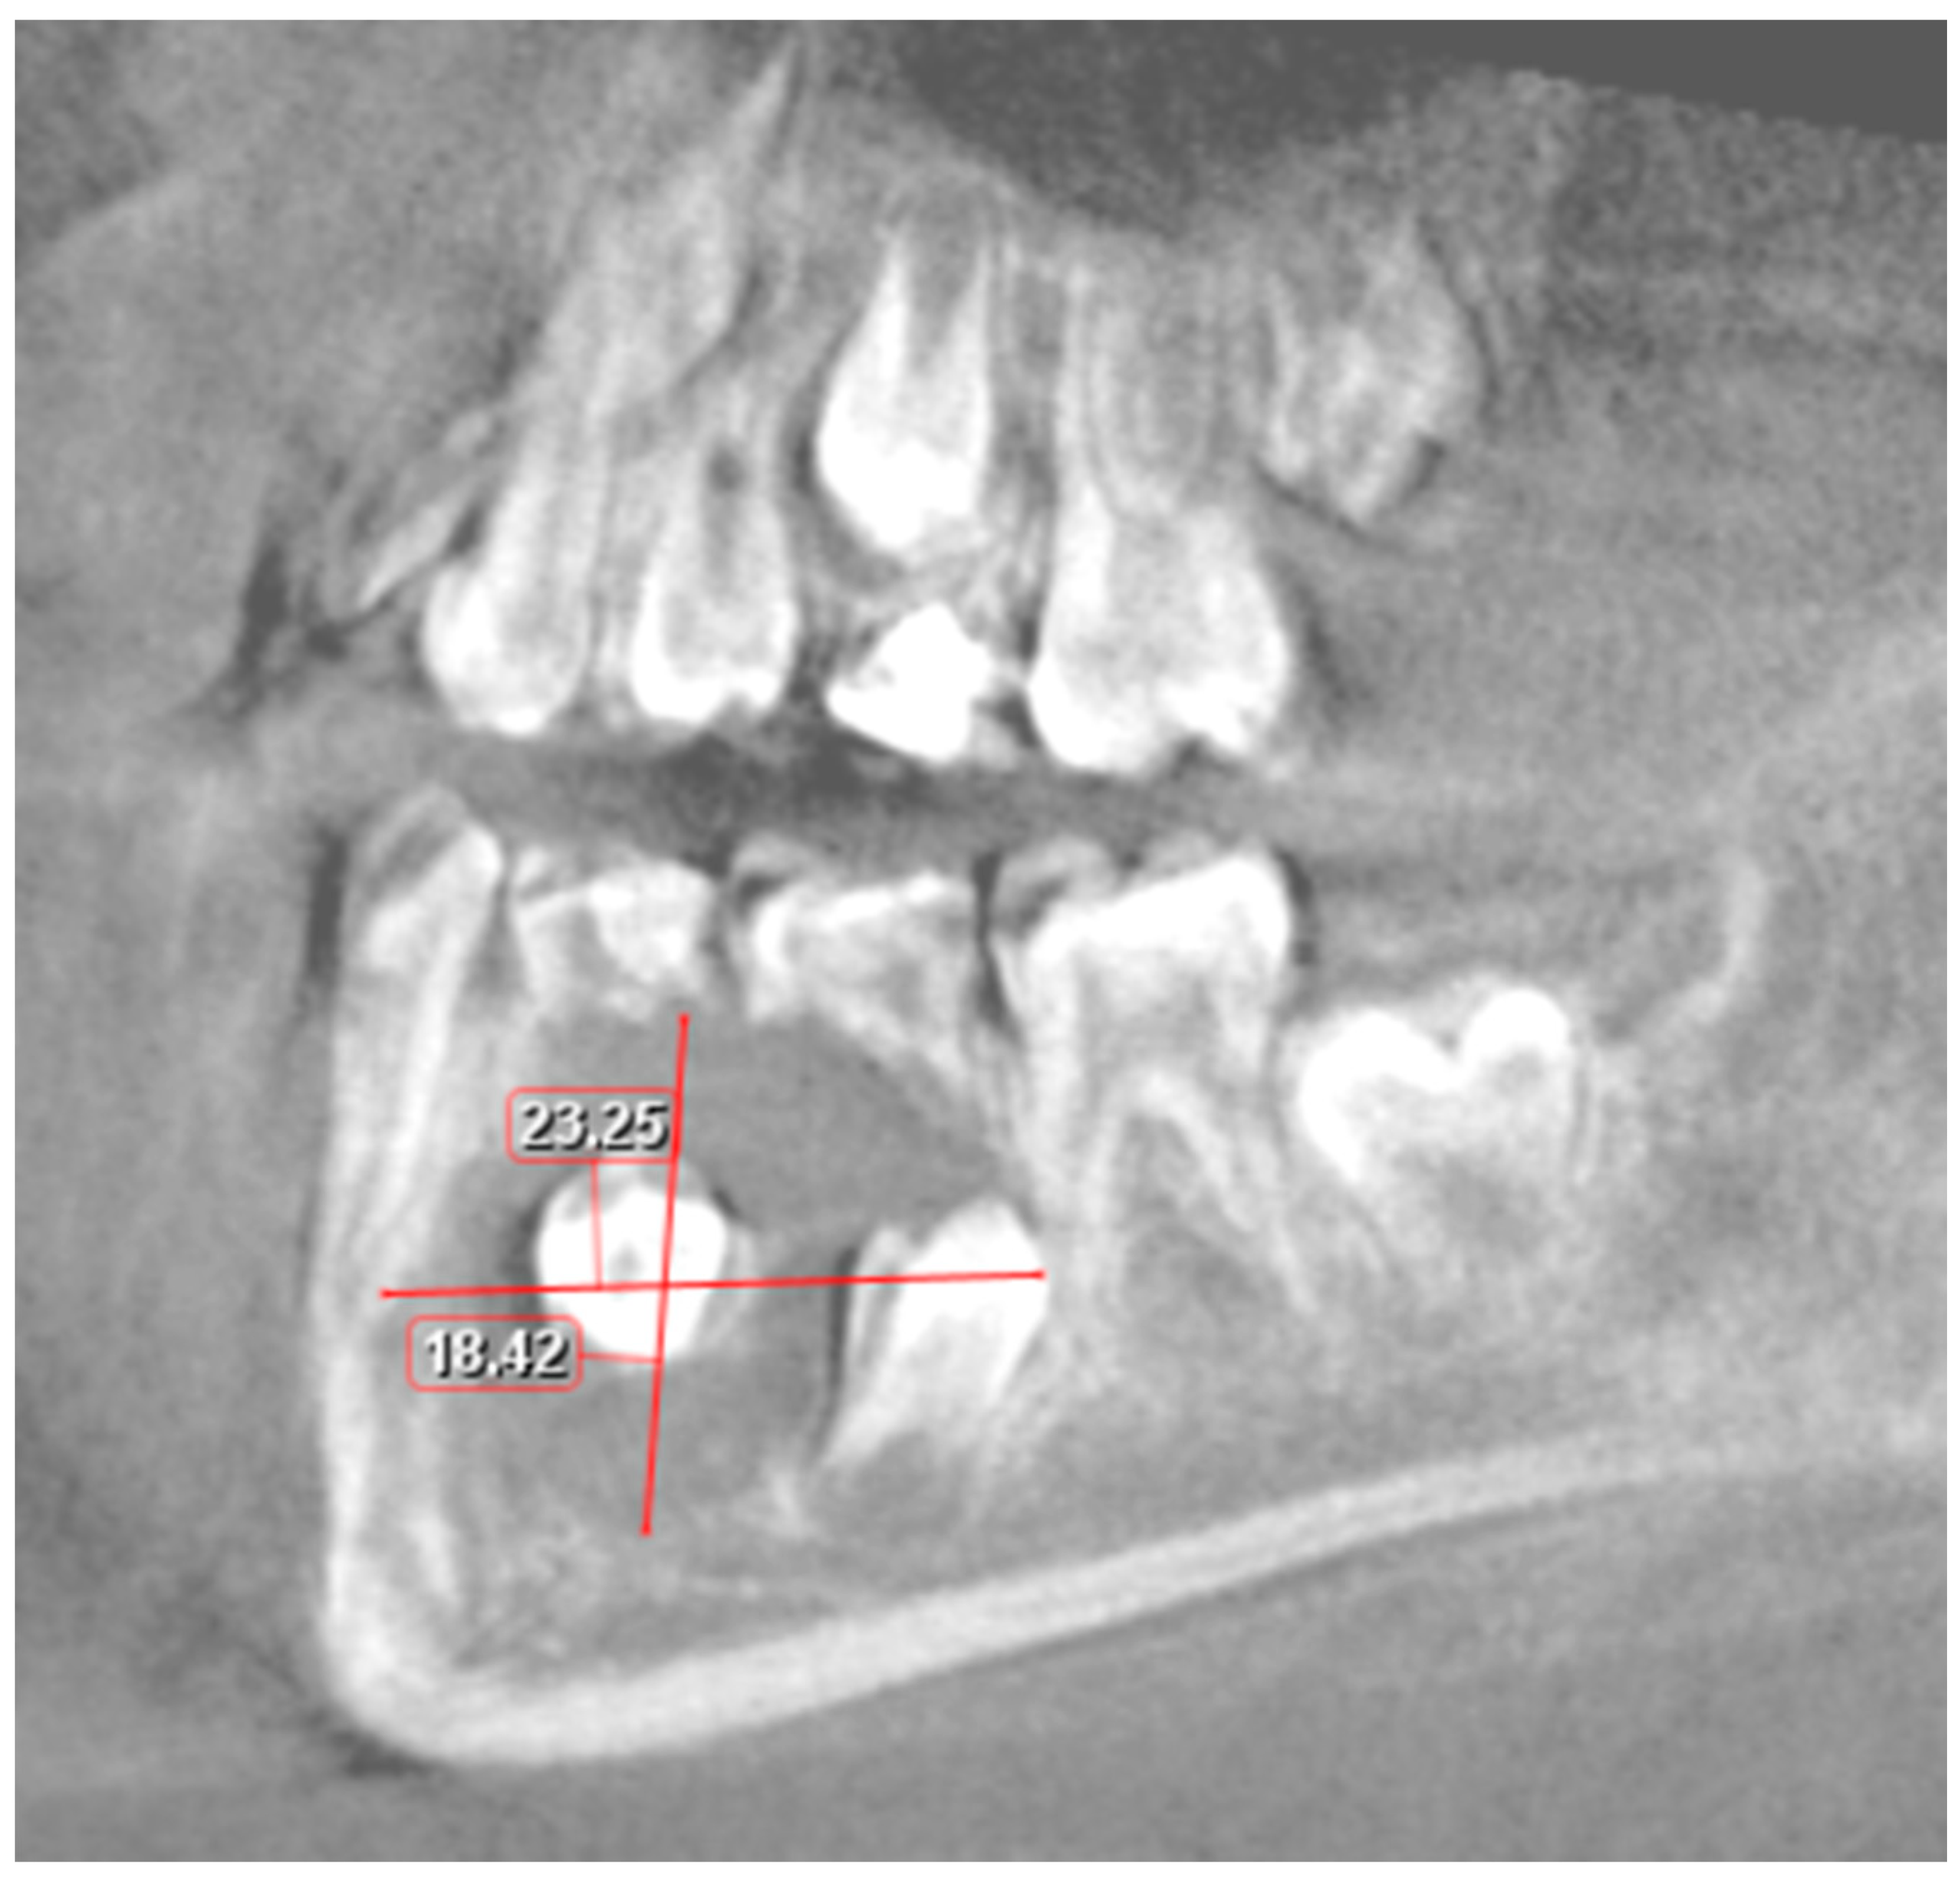

2. Case Report